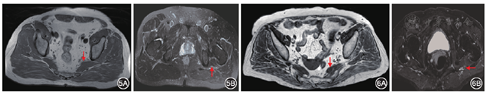

病例1:男性PS患者,57岁,习惯长期蹲坐且习惯钱包置于臀部口袋,其压痛点位点位于梨状肌体表投影(PM组患者),治疗前MRI检查示T2加权像轴位图像显示患侧(左侧)梨状肌形态较健侧(右侧)梨状肌形态轻度肥厚改变;左侧坐骨神经信号明显增高,水肿征象。提示患者梨状肌肥厚合并坐骨神经压迫损伤(图5)。

病例2:女性PS患者,81岁,有长期不良坐姿习惯,其压痛点位点解剖位点位于梨状肌上孔区域(SPF组患者),治疗前MRI检查示T2加权像轴位图像显示患侧(左侧)梨状肌形态与健侧(右侧)梨状肌形态未见明显异常;左侧坐骨神经信号明显增高,水肿征象。提示不良坐姿诱因可导致患者坐骨神经挤压损伤(图6)。